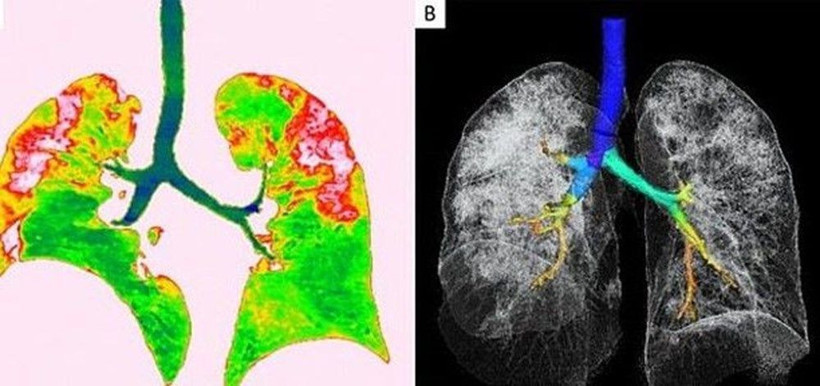

Wuhan'a seyahat ettikten sonra corona virüse yakalanan 54 yaşında bir kadının bilgisayarlı tomografi taramaları da akciğerlerinde hava boşluklarının kısmen dolduğunu gösteriyor. Solda yer alan fotoğrafta kırmızı olarak görülen alanlarda nodüller, sağ tarafta ise akciğer ve trakeanın üç boyutlu görüntüsü yer alıyor. Beyaz alanlarda corona virüsün tahribi görülüyor.